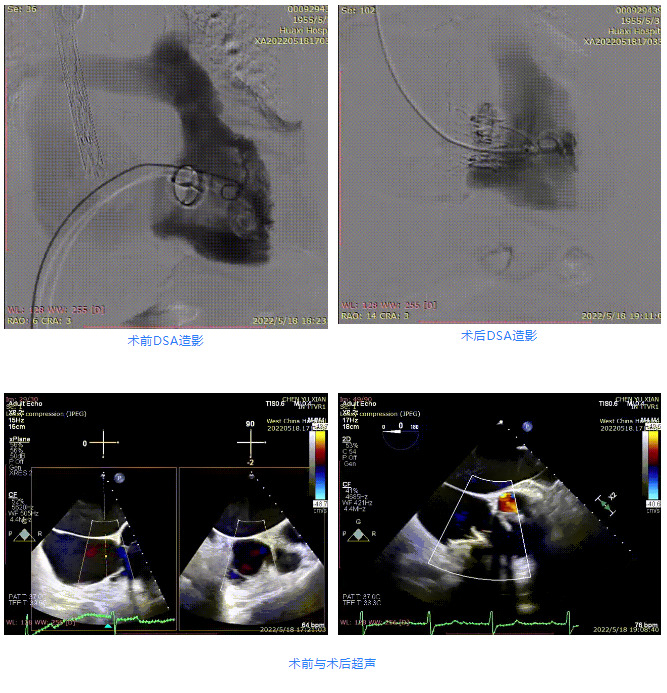

患者為67歲女性,主訴“活動后心悸、心累5年余”,偶有雙下肢水腫,無頭暈、暈厥史。20余年前,患者于本院行二尖瓣機械瓣置換術,有高血壓和糖尿病病史,心功能Ⅲ級。術前超聲報告顯示,全心增大,左房為著,三尖瓣大量反流Vmax=2.5m/s,PG=24 mmHg,三尖瓣瓣膜稍增厚,回聲稍增強;術前CT評估顯示,瓣環(huán)大小為41.4mm,瓣環(huán)平面與室間隔夾角為104°。

根據(jù)術前評估結(jié)果,郭應強教授團隊為患者量身定制了手術策略,決定使用LuX-Valve Plus經(jīng)血管三尖瓣置換系統(tǒng)開展手術治療。手術在全麻下進行,采用經(jīng)右側(cè)頸靜脈入路,在經(jīng)食道超聲和DSA的指引下調(diào)整輸送器角度以達到正確位置,勾住前瓣后逐步釋放盤片,盤片打開后順利扎針,最終完成瓣膜植入,輸送器撤出。術后超聲提示人工三尖瓣同軸性良好,瓣架固定牢靠,無反流和瓣周漏,術后三尖瓣平均跨瓣壓差為1 mmHg。